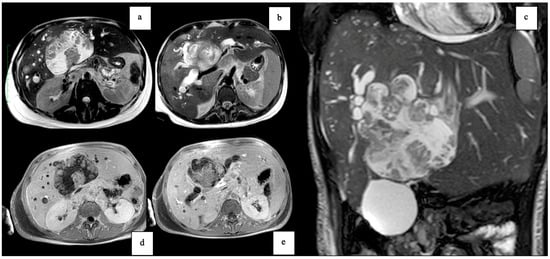

| Feature | Case 1 | Case 2 |

| Patient Demographics | 60-year-old Caucasian male | 28-year-old Caucasian female |

| Clinical Presentation | Incidental discovery of an 8 × 8 × 9 cm hepatic cyst | Presented with dyspnea, vomiting, jaundice, fever |

| Initial Diagnosis | Suspected hydatid cyst | Simple cyst, later adenocarcinoma with metastases |

| Diagnostic Methods | MRI, MRCP, ERCP, histopathological examination | CT, MRI, laparoscopic liver biopsy, histopathological examination |

| Tumor Characteristics | Large cystic mass, thin walls, internal septa, papillary projections, enhancing solid components | Large lesion in left hepatic lobe, hyperintensity in T2-weighted images, restricted diffusion, contrast enhancement |

| Treatment | Cyst resection, cholecystectomy | Thrombectomy, chemotherapy, supportive care |

| Surgical Findings | Partially exophytic floating soft mass | Extensive intrahepatic metastases, vascular involvement |

| Histopathological Findings | IPNB with foci of adenocarcinoma, oncocytic appearance, varying degrees of dysplasia, mucus within cyst | Adenocarcinoma with papillary clear cell and mucinous appearance, gland ectasis, cystic or pseudocystic aspects |

| Follow-up and Outcome | Initial recurrence-free survival for 8 years, recurrence treated with left hepatectomy, patient alive at 33 months post-second surgery | Disease progression despite aggressive management, patient died from hepatic failure |